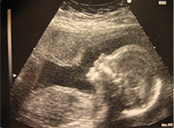

Types of Scans

Viability Scan

Conducted around 6 - 8 weeks of pregnancy, this ultrasound is performed to determine early pregnancy, the number of fetuses and gestational age, as well as the expected date of delivery. This scan is also used to exclude ectopic pregnancies.

Screening Scan

Conducted around 20 - 22 weeks of pregnancy. This fetal anomaly screening scan is performed to analyse the structural anatomy of the fetus and to screen for any structural anomalies. At this stage, the placental location, amount of amniotic fluid and the growth of the fetus is analysed.

Growth Scan

Conducted around 30 - 32 weeks of pregnancy. The growth scan is performed to assess the fetus' growth trend, evaluate the placental location prior to childbirth, to ensure a healthy volume of amniotic fluid is present and to observe the fetal movement. Coloured doppler ultrasound is also used to ensure optimum and healthy blood flow to the baby.